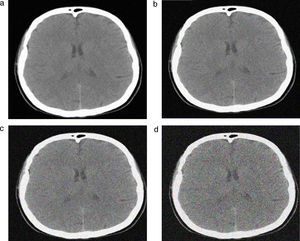

Las imágenes originales obtenidas a los niveles de referencia fueron procesadas a través del software Image J 1.43u. Este software modifica las imágenes ya adquiridas agregando el ruido a partir de la desviación estándar para generar las imágenes simuladas a diferentes valores de mAs (fig. 2).